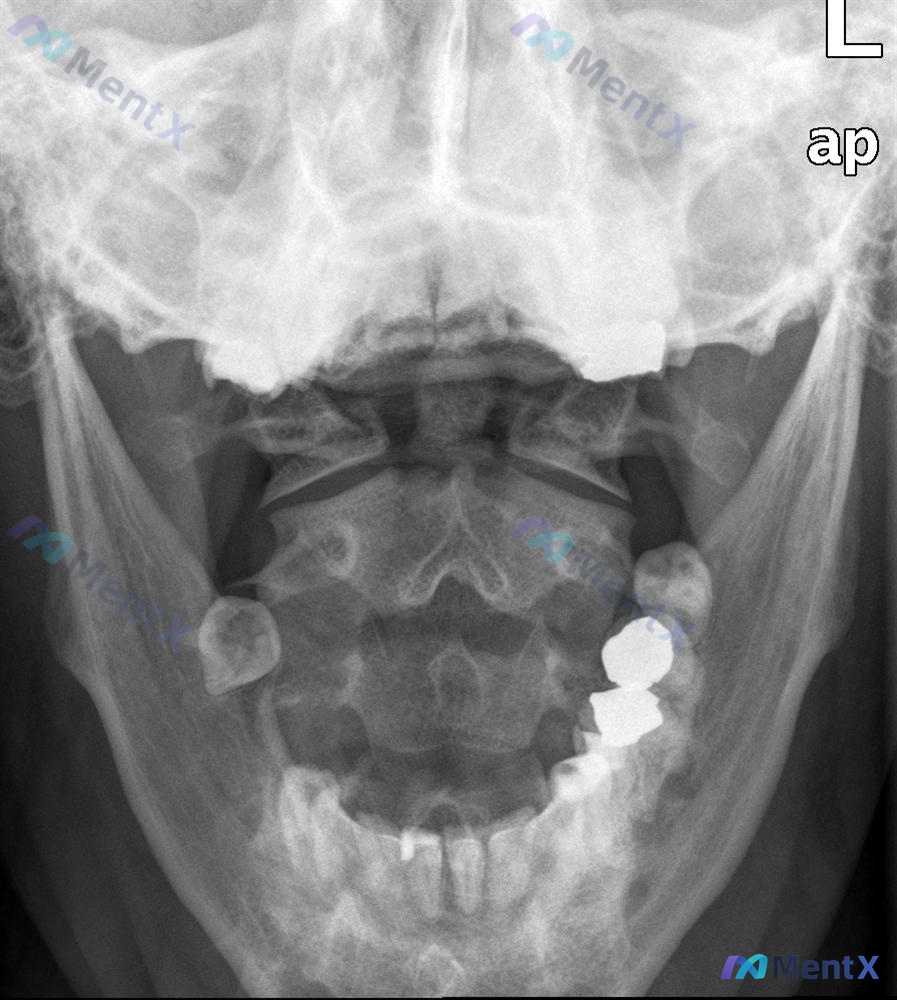

- 影像:张口颈椎X光片、矢状位CT、CT轴位血管造影

影像分析提示:

- 枢椎(C2)齿状突基底部骨折,骨折块与椎体分离

- 齿状突骨折块伴随寰椎向前移位,寰枢关节不稳/半脱位

- 寰枢复合体稳定性完全丧失,需警惕脊髓/延髓压迫风险